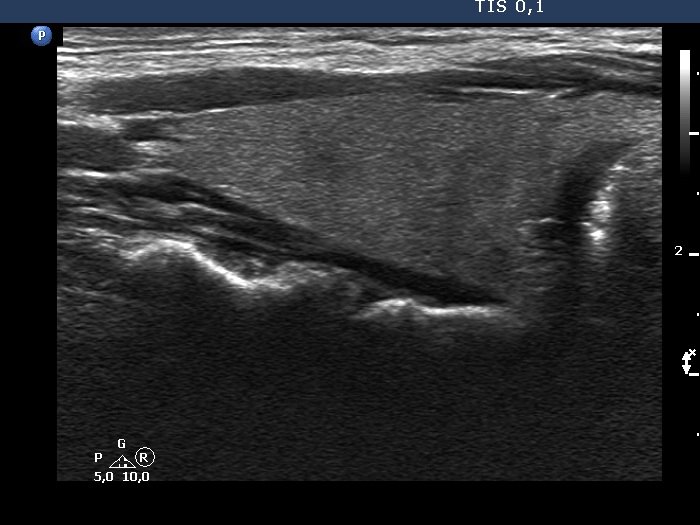

Right lobe, longitudinal scan

Right lobe, longitudinal scan. There is a thickening of the connective tissue but not to as extent as seen on transverse view.